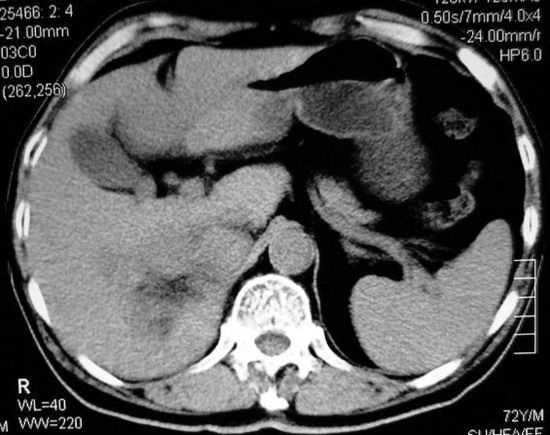

以下是引用杀毒软件在2008-11-17 19:15:00的发言:[br]考虑------右肾癌合并肾静脉---同侧肾上腺受侵可能性大

以下是引用zjzjr在2008-11-17 20:45:00的发言:[br]考虑------右肾癌合并肾静脉---同侧肾上腺受侵可能性大及腹膜后淋巴结转移.